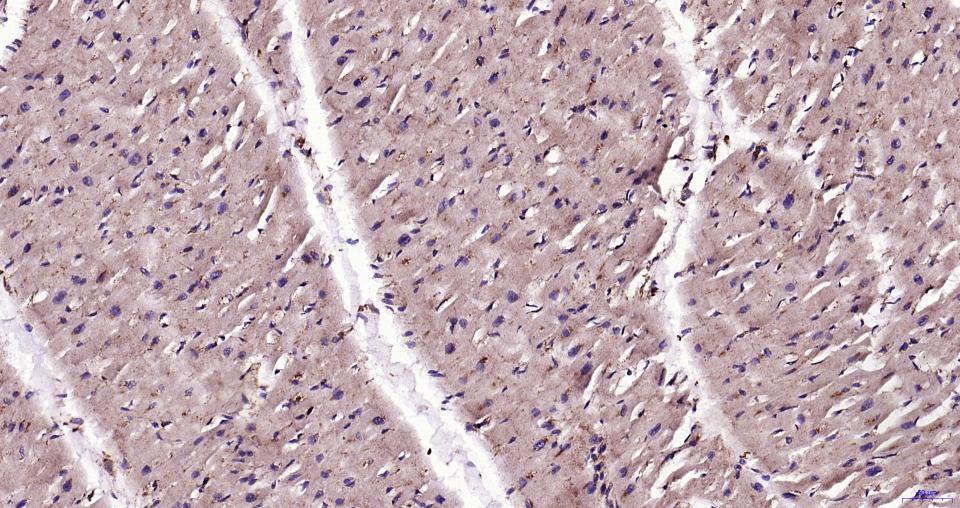

Paraformaldehyde-fixed, paraffin embedded Human Heart; Antigen retrieval by boiling in sodium citrate buffer (pH6.0) for 15 min; Antibody incubation with LAMP1 Monoclonal Antibody, Unconjugated(bsm-61375R) at 1:200 overnight at 4°C, followed by conjugation to the SP Kit (Rabbit, SP-0023)and DAB (C-0010) staining.